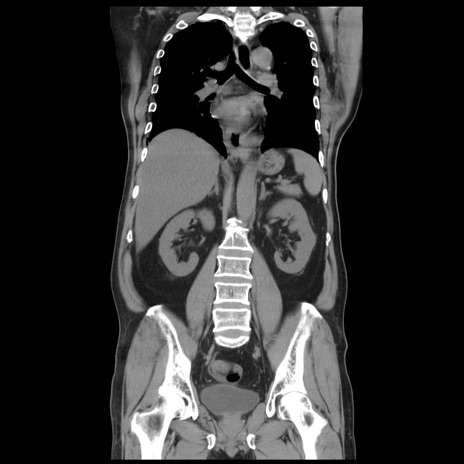

症例20(冠状断像)

【症例】 60歳代男性

【主訴】 腹部膨満、嘔吐

【現病歴】5日前頃より倦怠感を認め食事量減少し4日前の朝嘔吐、食事摂取困難となった。 3日前近医受診し点滴施行され整腸剤などを処方された。 当日他院を受診し、腹部膨満著明、炎症反応の上昇(CRP10.8、WBC11200)あり、紹介受診となる。

【身体所見】 意識JCS1 受け答えがはっきりしないBP 111/57mHg、 P 67bpm、、BT35.2°C、SpO2 97%(RA)、 腹部:膨隆、打診で鼓音あり、全体的に圧痛有り、腸蠕動音(-)、反跳痛ははっきりせず。

【データ】WBC 11400、CRP 14.20